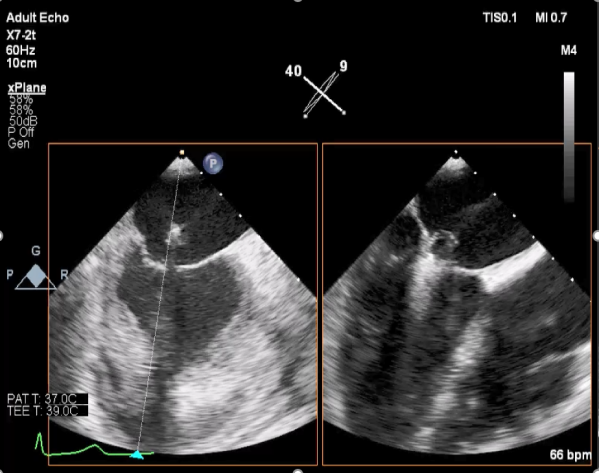

二尖瓣联合部切面引导第一枚XTR夹子转向病变区域并逐渐进入左室

第一枚XTR夹子到达病变区域捕获瓣叶并逐渐夹闭

XTR夹子释放,残余部分返流

三维超声心动图显示第一枚XTR夹子释放,残余返流主要位于外侧

引导第二枚XTR夹子转向外侧残余病变区域并逐渐进入左室

第二枚XTR夹子释放,返流明显减少

三维超声心动图显示第二枚XTR夹子释放